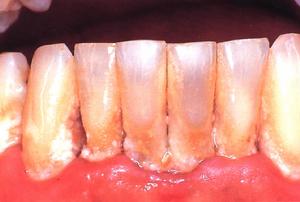

3、逆行性牙髓炎:是牙周病患牙的牙周組織破壞後,感染通過側、副根管或根尖孔進入牙髓引起的牙髓炎症。患牙伴有嚴重的牙周病,同時表現出牙周炎、根尖周炎和牙髓炎的多種特性。有自發性和陣發性疼痛,對冷、熱刺激敏感或有放散痛等急性牙髓炎的表現;也可表現為牙齒鈍痛、脹痛,無明顯自發痛,對冷、熱刺激敏感等慢性牙髓炎的症狀;檢查可見深的牙周袋,或創傷性咬合,牙齒鬆動、叩痛;X線片示根尖周牙槽骨吸收。治療可選用開髓術、根管治療術。

牙齒潔治不可逆性牙髓炎:治療方法以去除牙髓,保存患牙為目的,如根管治療術。

清除牙石:你應該定期去牙醫處洗牙,以清除牙石,預防牙齦炎。